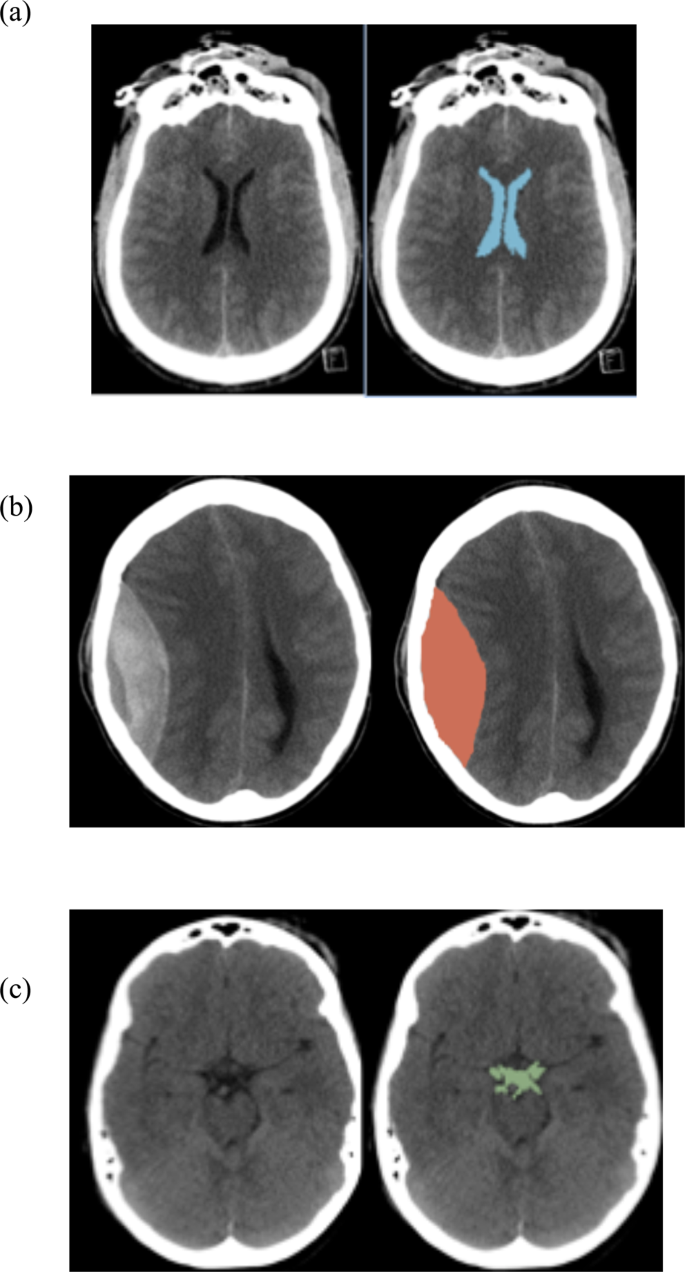

Csf is of lower density than the grey or white matter of the brain, and therefore appears darker on ct images.

Basal ganglia, group of nuclei (clusters of neurons) in the brain that are located deep beneath the cerebral cortex (the highly convoluted outer layer of the anatomy and connections. The foramen of magendie and the foramina of luschka drain csf into the cisterna. The two dark lines medially of the thalamus are the internal cerebral veins.